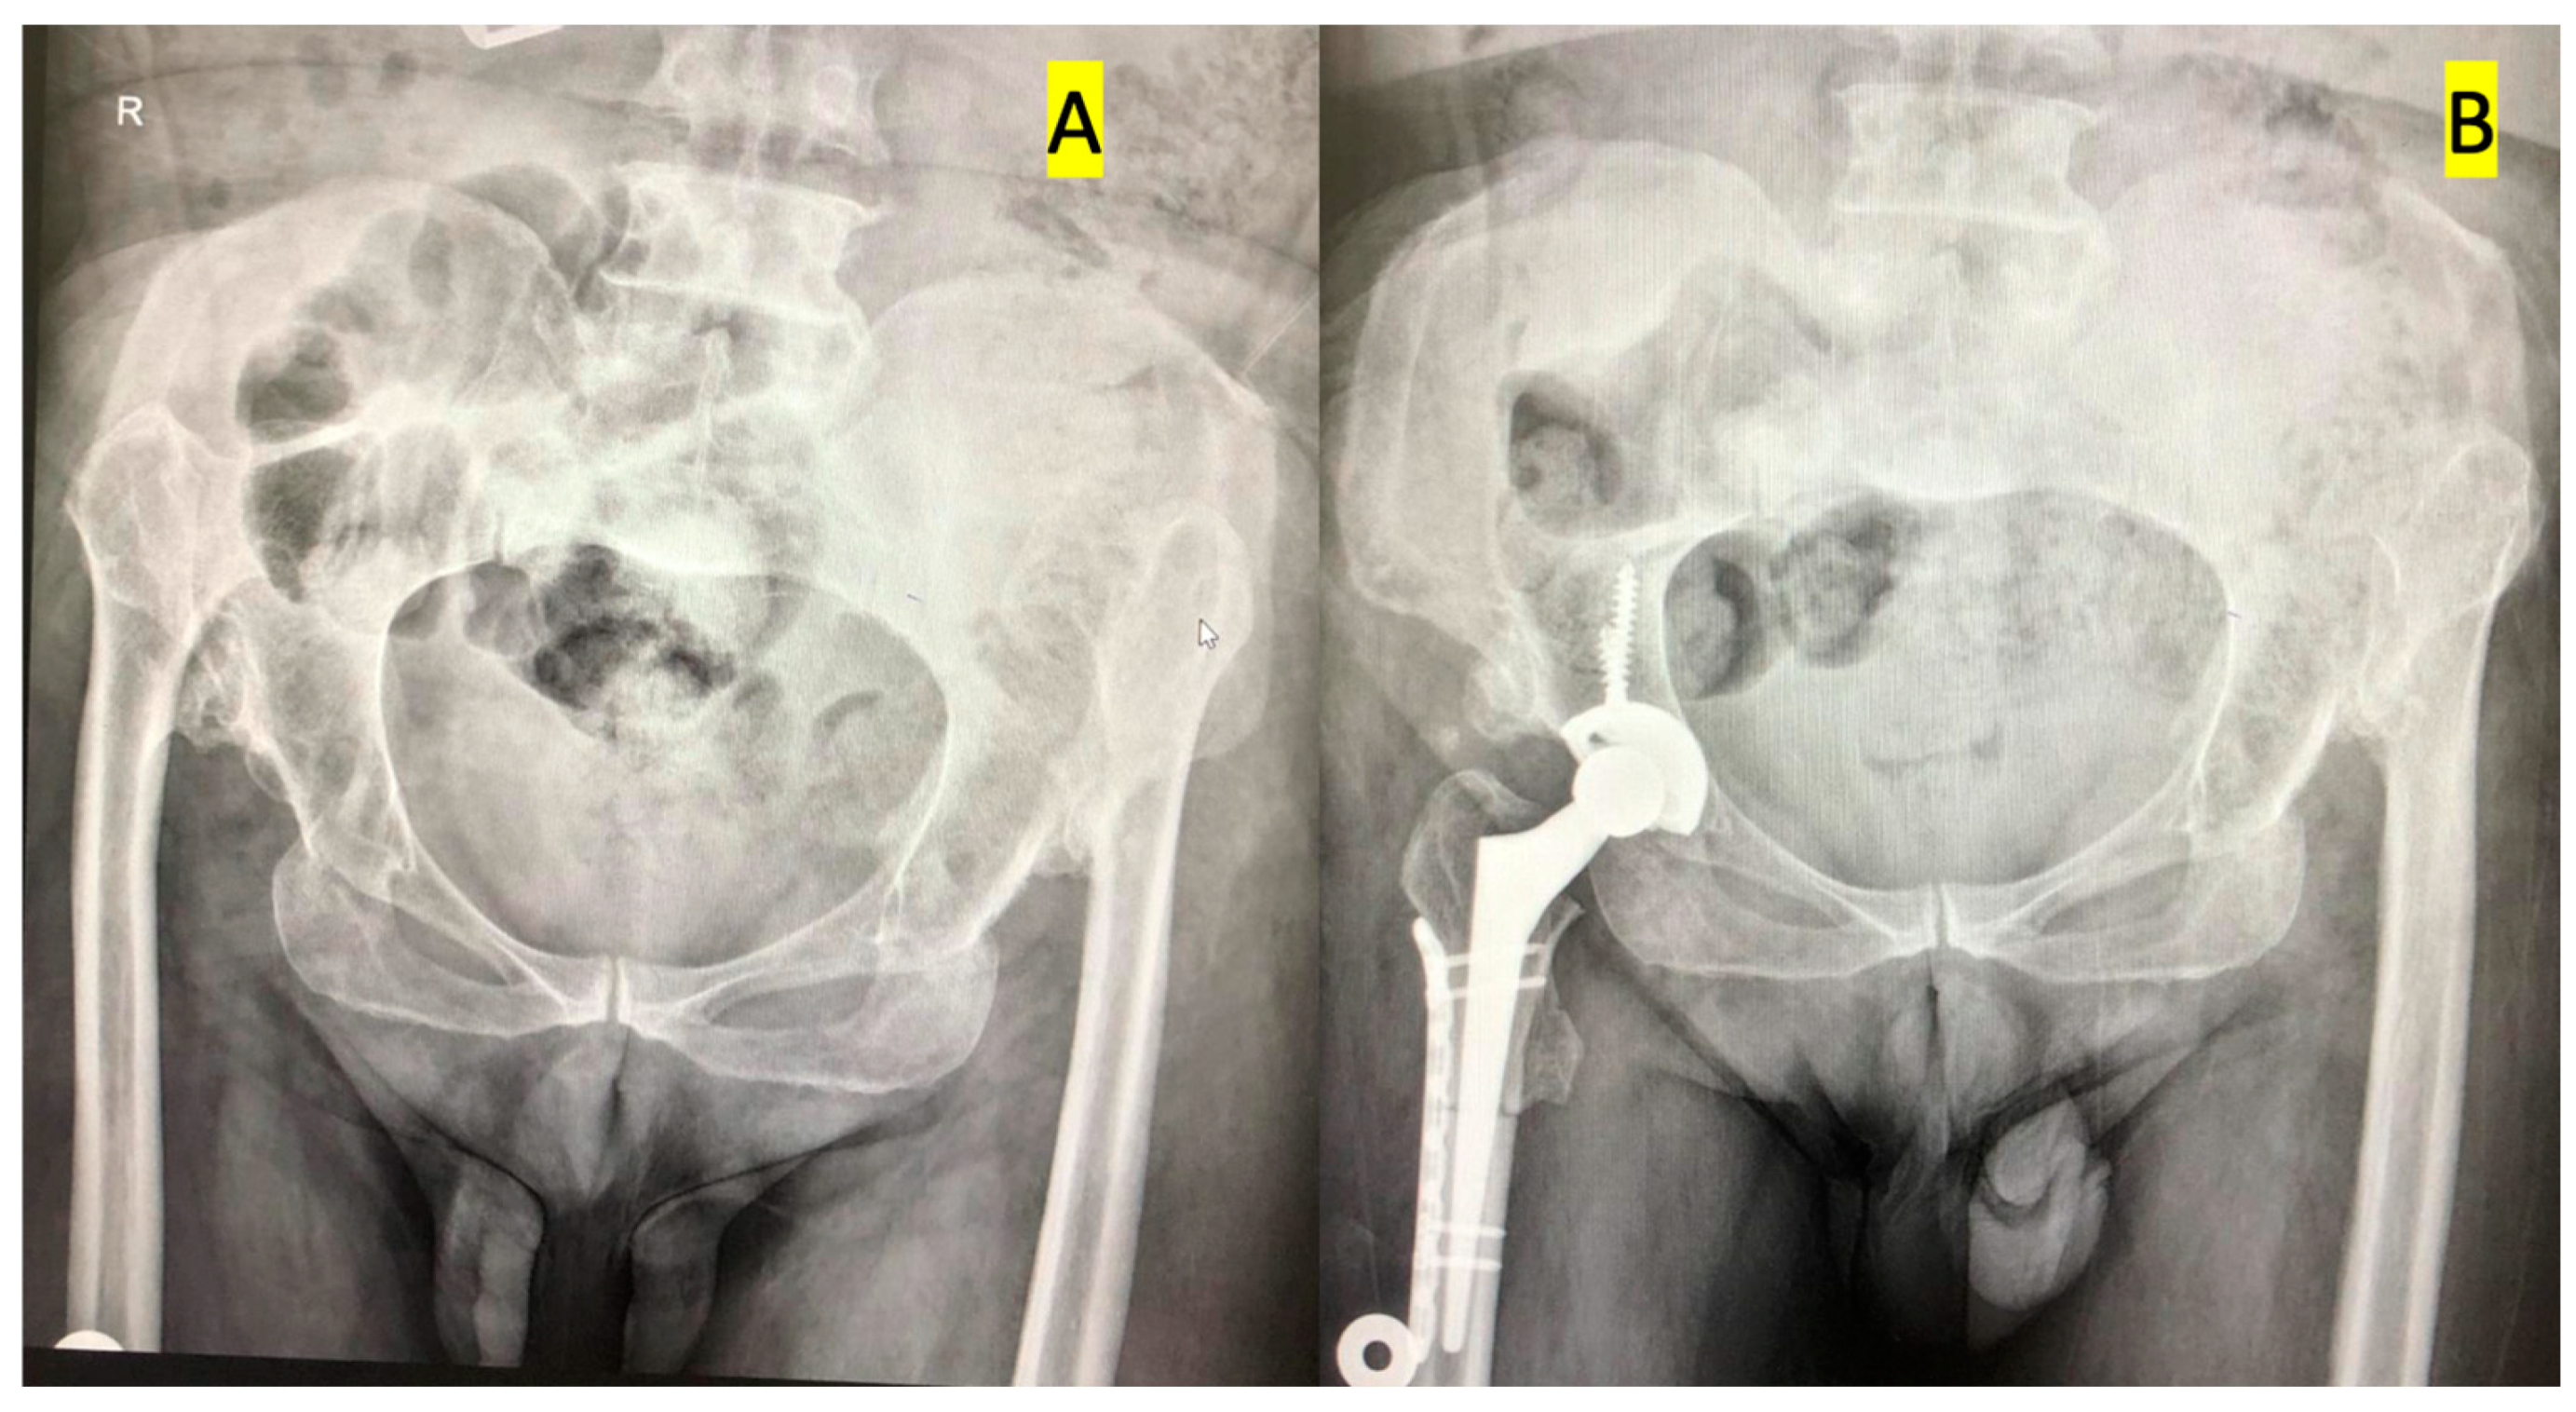

Percutaneous adductor tenotomy was performed to enable distal relocation of the femur in patients who had limited abduction before surgery. The procedure may be summarized as follows: Patients were placed in the lateral decubitus position on the operating table. The pelvis was supported and splinted from the pubis to the sacrum. A posterolateral incision was used in all patients. The tensor fascia lata was longitudinally cut, the external rotator muscle was suspended by forcing the leg to internal rotation, and finally, the capsule was cut to reach the bone. The femur neck was cut in a standard way, and the location of the acetabulum was determined by following the inferior adhesion site of the capsule. Surrounding osteophytes and hypertrophic soft tissues were resected and cleared for a better view of the acetabulum. Starting with the smallest engraver, the acetabulum was engraved and prepared to ensure proper anteversion and inclination. The acetabular component was fixed to the true acetabulum by using an uncemented press fit and 2–3 titanium screws. The medulla of the femur was carved with carvings. Two points are placed on the proximal and distal parts in the same plane as the line along which the osteotomy was conducted. Transverse subtrochanteric osteotomy was performed from 1–2 cm distal to the minor trochanter. The proximal femur was sutured at 30 degrees retroversion of the proximal femur k line. Finally, the hip joint was reduced (

Figure 1). The anteversion angle of the femur was increased in Group 1, unchanged in Group 2, and decreased in Group 3. The decision was made according to standard indications, radiological results, and intraoperative evaluation of patient anatomy.